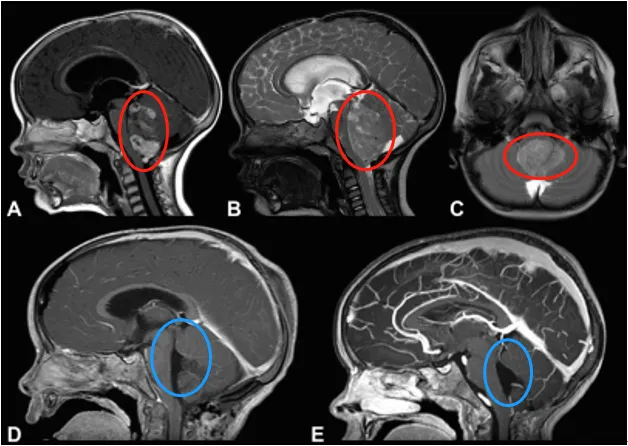

彥彥所患的第四腦室室管膜瘤在臨床上并不罕見,占兒童中樞神經(jīng)系統(tǒng)腫瘤的2%-9%,是兒童第三大常見顱內(nèi)腫瘤,其中四分之三的患兒和彥彥一樣,腫瘤恰好長在第四腦室。

或許很多家長會疑惑:“第四腦室”是什么地方?簡單來說,它位于顱內(nèi)深處,緊鄰腦干——這個被稱為“生命中樞”的部位,控制著唿吸、心跳、吞咽等基本生命活動。

很快,在Rutka教授主刀之下,手術(shù)使用枕下開顱和C1椎板切除術(shù)——這是針對第四腦室腫瘤的經(jīng)典術(shù)式,需要在高倍顯微鏡下精準(zhǔn)分離腫瘤與腦干、神經(jīng)的粘連。術(shù)中每一步都格外謹(jǐn)慎,既要徹底切除腫瘤,又要確保不觸碰任何關(guān)鍵神經(jīng)。最終彥彥手術(shù)順利。

第四腦室室管膜瘤